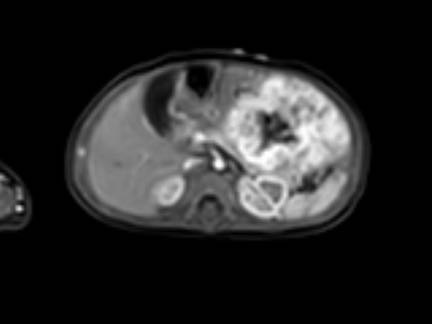

Hình ảnh MRI của một bé gái chín tháng tuổi có khối u ở bụng trái. MRI cho thấy khối u tuyến thượng thận trái, một phần đặc, một phần nang. Có nhiều di căn gan.

Khối u đã được sinh thiết. Có tình trạng chảy máu liên tục qua kim dẫn đường. Vào cuối thủ thuật, hai nút bọt gelatin đã được đặt vào (các dải tăng âm (mũi tên)).